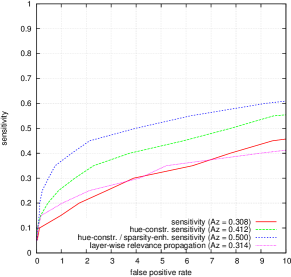

FROC curves are reported in Fig. 6 for ‘net B’; areas under the limited FROC curve for all three ConvNets are summarized in Table 3. It appears that the number of false alarms is rather large, particularly in the case of microaneurysm detection. The reason is that human experts primarily segmented the most obvious lesions, while screening algorithms need to focus on the most subtle lesions as well. In other words, many true lesions are counted as false alarms. Of course, this comment also applies to competing automatic solutions. To show the value of our detections, the proposed solution was compared in Fig. 7 to results reported in the literature, following the DiaretDB1 standardized procedure (see section 5.3.2). Most authors reported a single (sensitivity, specificity) pair: this is what we reported in Fig. 7. Some authors reported ROC curves; in that case, we also reported a single (sensitivity, specificity) pair: the one closest to the (sensitivity = 1, specificity = 1) coordinate. Note that all competing solutions (Kauppi et al., 2007; Yang et al., 2013; Franklin and Rajan, 2014; Kumar et al., 2014; Bharali et al., 2015; Mane et al., 2015; Dai et al., 2016) are trained at the lesion level, while ours is trained (in Kaggle-train) at the image level.

Three ConvNets were trained to detect referable DR in the Kaggle-train dataset, using the proposed heatmap optimization procedure. Then, we evaluated how well those ConvNets could detect lesions in the DiaretDB1 dataset, without retraining them. For lesion detection at the image level, they outperformed previous algorithms, which were explicitly trained to detect the target lesions, with pixel-level supervision (see Fig. 7). This superiority was observed for all lesions or groups of lesions, with the exception of ‘red lesions’. Experiments were also performed at the lesion level: for all lesion types, the proposed algorithm was found to outperform recent heatmap generation algorithms (see Table 3). As illustrated in two examples (see Fig. 9 and 10), the produced heatmaps are of very good quality. In particular, the false alarms detected on the vessels, in the vicinity of true lesions in the unoptimized heatmaps ( maps), are strongly reduced with sparsity maximization (, , ). These experiments validate the relevance of image-level supervision for lesion detectors, but stress the need to optimize the heatmaps, as proposed in this paper. Note that detection performance is not affected much by image quality: very good detections are produced in the blurry image obtained with a low-cost, handheld retinograph (see Fig. 10). This is a very important feature, which opens the way to automated mobile screening. However, it can be observed that the ‘AlexNet’ architecture, which achieves moderate DR detection results, also achieves poor detection results at the lesion level, even after heatmap optimization (see Table 3): to ensure good detection performance at the lesion level, the proposed optimization framework should be applied to ConvNet architectures that achieve good image-level performance.